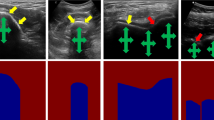

Segmenting both bone surface and the corresponding acoustic shadow are fundamental tasks in ultrasound (US) guided orthopedic procedures. However, these tasks are challenging due to minimal and blurred bone surface response in US images, cross-machine discrepancy, imaging artifacts, and low signal-to-noise ratio. Notably, bone shadows are caused by a significant acoustic impedance mismatch between the soft tissue and bone surfaces. To leverage these complementary features between these highly related tasks, we propose a single end-to-end network with a shared transformer-based encoder and task independent decoders for simultaneous bone and shadow segmentation. To share complementary features, we propose a cross task feature transfer block which learns to transfer meaningful features from decoder of shadow segmentation to that of bone segmentation and vice-versa. We also introduce a correspondence consistency loss which makes sure that network utilizes the inter-dependency between the bone surface and its corresponding shadow to refine the segmentation. Validation against expert annotations shows that the method outperforms the previous state-of-the-art for both bone surface and shadow segmentation.